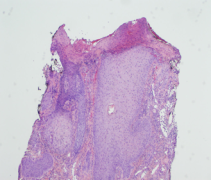

Samples of the involved tissue should be collected and evaluated with Gram stain, viral and fungal elements, and cultured for aerobic, anaerobic, and fungal disease. Biopsy with histopathologic evaluation is required to rule out other diagnoses. Histology reveals non-specific inflammatory changes, most notably ulceration with adjacent lichenification and epidermal and dermal scarring with mild mixed inflammatory infiltrate (Figure 4).[4] Acanthosis, hypergranulosis, and hyperkeratosis are also common.[13] Laboratory work-up is typically unremarkable but could be undertaken if the diagnosis remains unclear after biopsy and should include infectious, autoimmune, and vasculitis labs. Neuroimaging is recommended if the underlying cause of TTS is unclear from the patient’s history.[2]